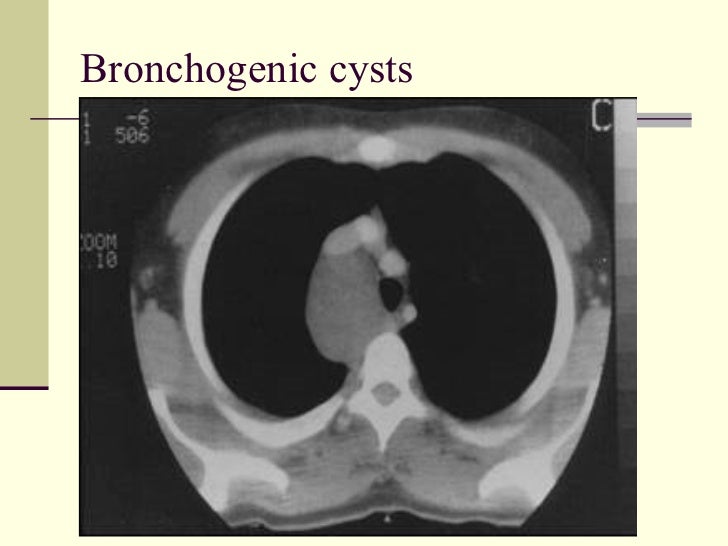

59. 67. <ul><li>Middle Mediastinal Masses </li></ul><ul><li>1. Lymphadenopathy </li></ul><ul><li>2. Aneurysms </li></ul><ul><li>3. Esophageal duplication </li></ul><ul><li>4. Bronchogenic cysts </li></ul>

60. 68. Bronchogenic cysts